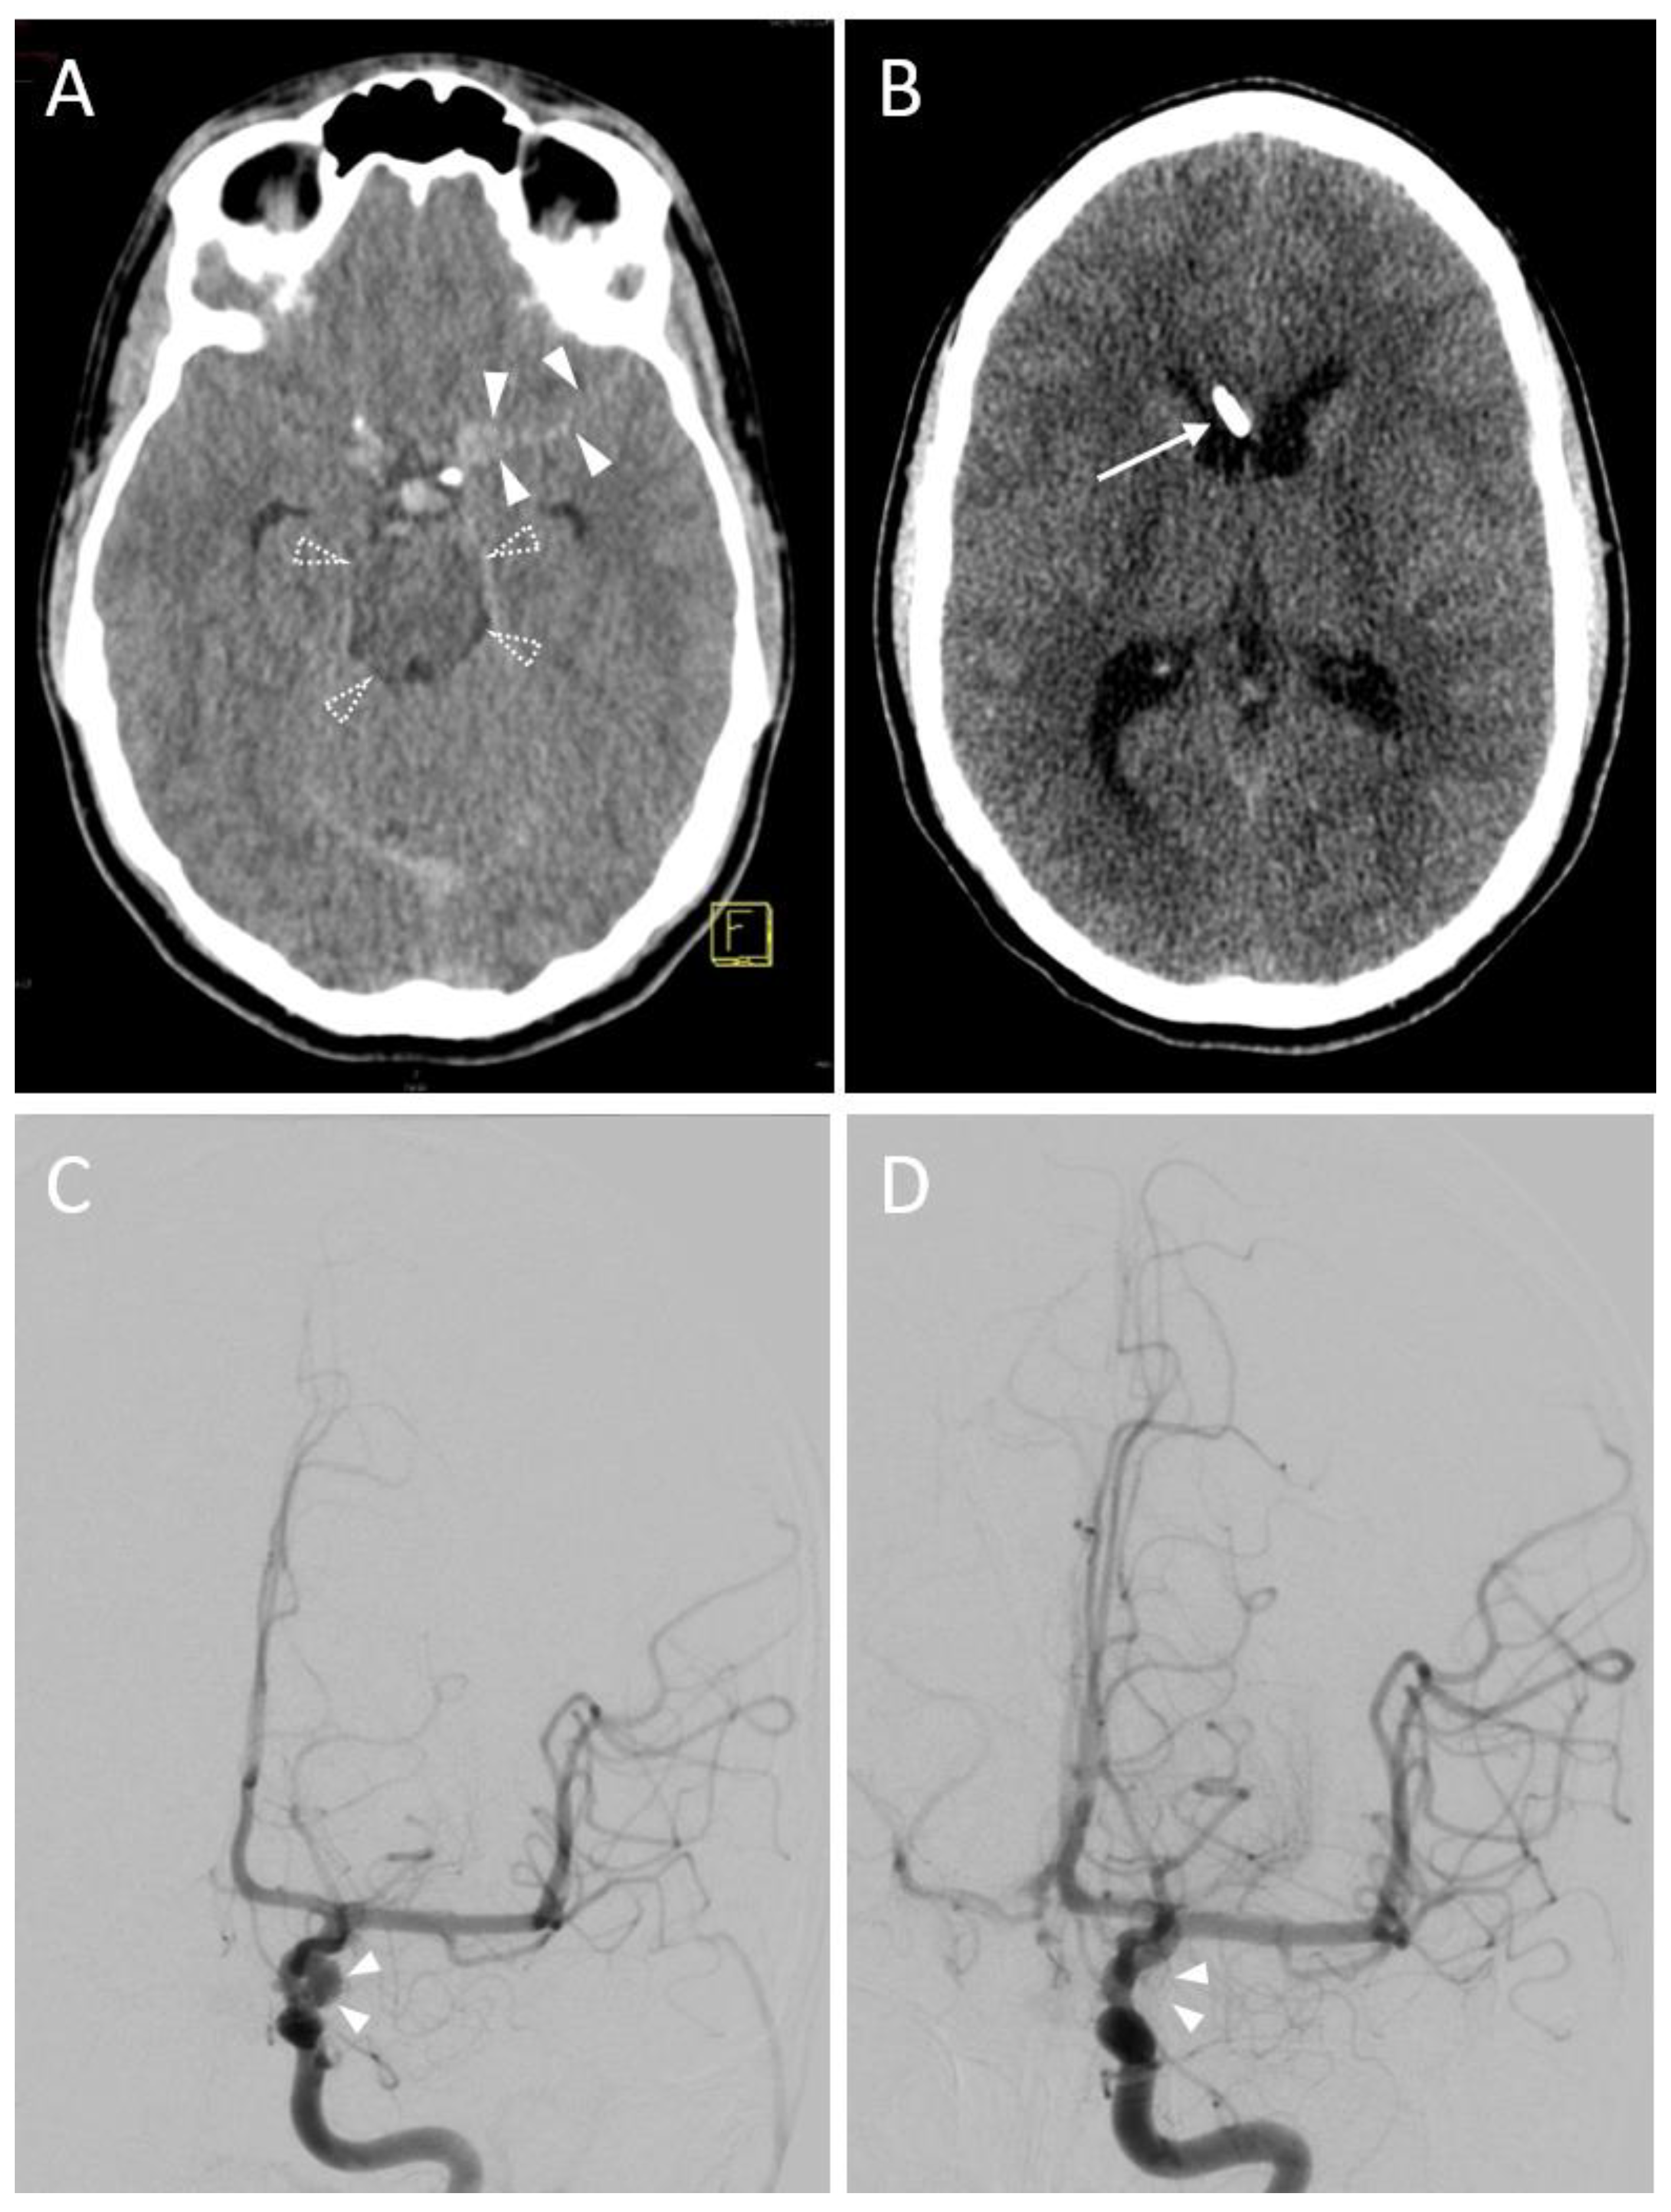

In the majority of sessions (n = 28, 77.8%), a Kakarla I EVD position was documented after the first control CT scan (Figure 2).

Figure 2.

A 16-year-old male with a subarachnoid hemorrhage from an aneurysm of the left internal carotid artery. (A) Planning a CT scan revealed a subarachnoid hemorrhage (Fisher Grade IV). Blood collections are shown in the perimesencephalic cistern (transparent arrowheads) and the lateral fissure (opaque arrowheads). Due to beginning hydrocephalus, indication for EVD placement was given. Yellow graphic: orientation cube (f: frontal). (B) Control CT scan. Successful EVD placement in the right frontal horn with tip next to the septum pellucidum (Kakarla I). (C) Digital Subtraction Angiography (DSA) before endovascular treatment. Source of bleeding is a broad-based saccular aneurysm at the outlet of the left posterior communicating artery with a maximum diameter of 6.5 × 5.0 mm (arrowheads). (D) DSA control scan after coil placement depicts complete elimination of the aneurysm sac.